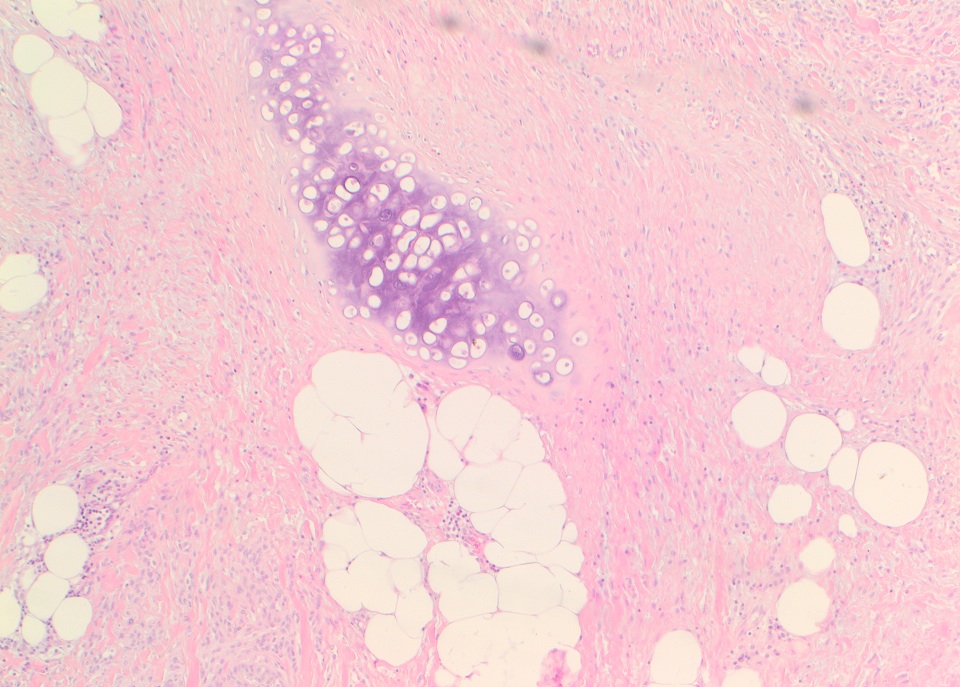

Micro images:

The conventional histologic appearance is of bland fibroblast-like spindle cells with relatively short, stubby nuclei. The cells are interspersed between collagen bundles and a variable amount of adipose tissue. The stroma can show hyalinization and / or myxoid change. Mast cells may be conspicuous (Goldblum: Enzinger and Weiss's Soft Tissue Tumors, 6th ed, 2013, Am J Surg Pathol 2016;40:361). Several different variants of MTMF have been described: cellular, infiltrating, collagenized / fibrous, lipomatous, myxoid, epithelioid and deciduoid-like. Areas of smooth muscle, bone and cartilage can be seen (Am J Surg Pathol 2009;33:1085). Rare tumors may show a neurilemmoma-like pattern. "Symplastic" or degenerative cytologic atypia - enlarged, hyperchromatic, multinucleated cells - can be present (Am J Surg Pathol 2016;40:361).

Micro images:

The conventional histologic appearance is of bland fibroblast-like spindle cells with relatively short, stubby nuclei. The cells are interspersed between collagen bundles and a variable amount of adipose tissue. The stroma can show hyalinization and / or myxoid change. Mast cells may be conspicuous (Goldblum: Enzinger and Weiss's Soft Tissue Tumors, 6th ed, 2013, Am J Surg Pathol 2016;40:361). Several different variants of MTMF have been described: cellular, infiltrating, collagenized / fibrous, lipomatous, myxoid, epithelioid and deciduoid-like. Areas of smooth muscle, bone and cartilage can be seen (Am J Surg Pathol 2009;33:1085). Rare tumors may show a neurilemmoma-like pattern. "Symplastic" or degenerative cytologic atypia - enlarged, hyperchromatic, multinucleated cells - can be present (Am J Surg Pathol 2016;40:361).